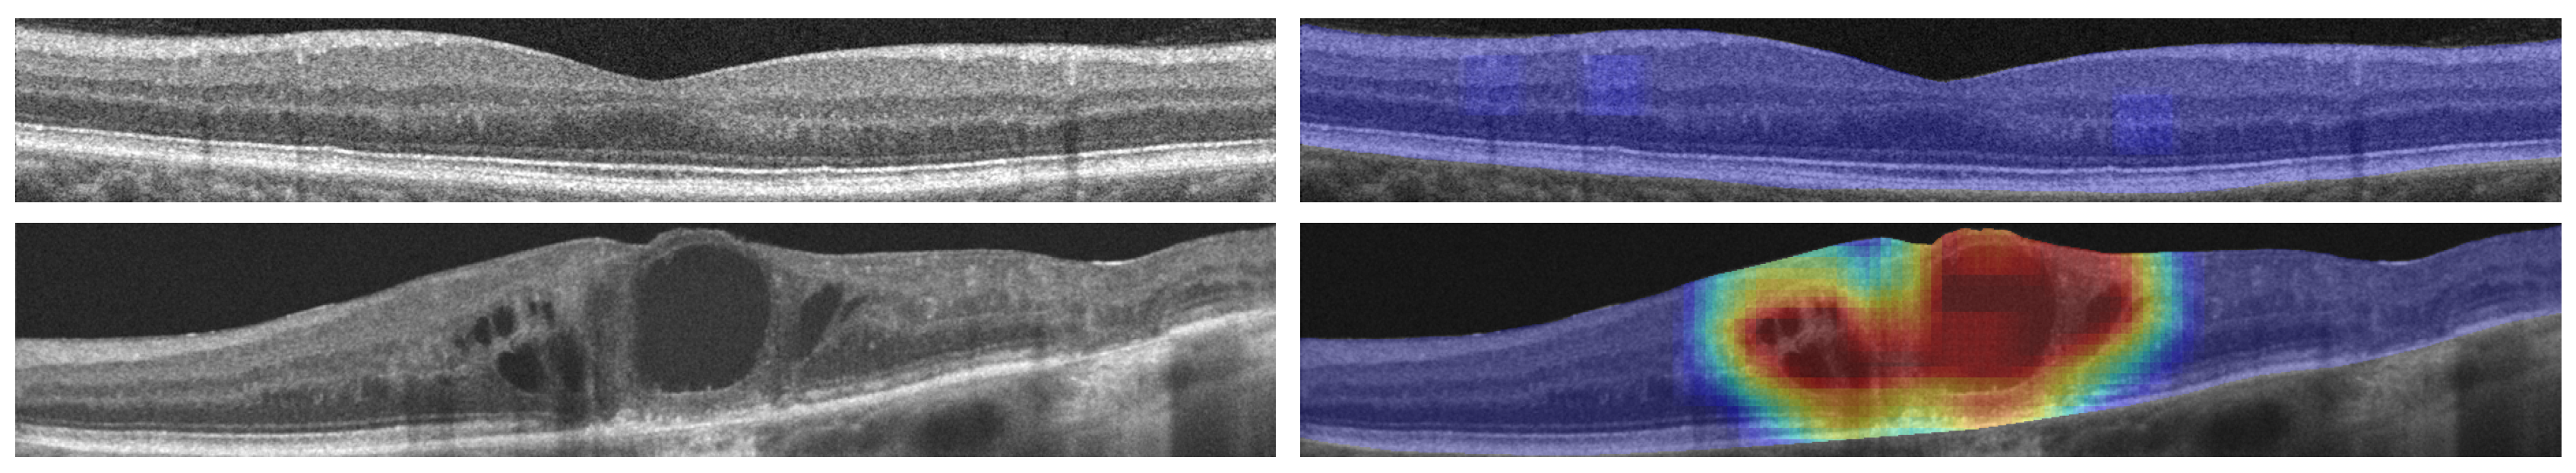

The network was trained using a base dataset of 3247 samples from two different representative OCT capture devices, increased by means of data augmentation. Additionally, the training of the network was done by using an automated control of the learning rate depending on the validation results, and stopped by means of an early-stopping criteria that detects when the training quality has stagnated. To further study the capabilities of our system, the training process was repeated 50 times, randomly distributing the training and validation datasets and recalculating the data augmentation procedure. After all the repetitions, the system attained a satisfactory mean test accuracy of 97.45% ± 0.7611 and a mean area under the ROC curve (AUC) of 0.9961 ± 0.0029. Regarding maps, as shown in Figure 1 and Figure 2, the DenseNet architecture is able to successfully represent both pathological and healthy regions in different representative devices of the domain.

Figure 2.

Results from a Cirrus HD-OCT OCT device from Carl Zeiss Meditec, including a healthy and a pathological example.